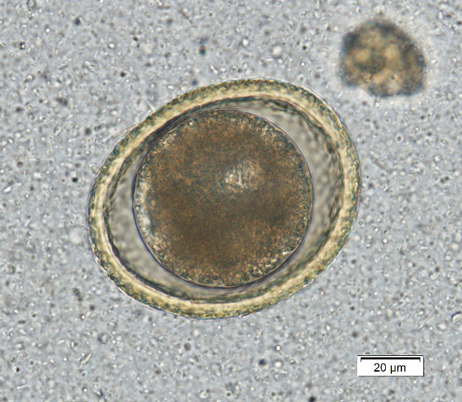

Toxocara canis is the dog roundworm and T. cati is the cat roundworm. Their species’ names help keep them straight, and there are some morphologic characteristics that help us differentiate them under the scope. Both T. canis (Figure 1a) and T. cati (Figure 1b) are round to oval eggs with thick, pitted, golden yellow shells. Within the shell is a dark brown developing embryo that is only one circular mass in fresh samples but can start to divide as a sample ages. Toxocara canis is approximately 75 µm x 85 – 90 µm compared to the 65 µm x 75 µm of T. cati, which make size the primary differentiator between these two eggs.

In addition, the pitting of the shell of T. canis makes the egg look like a golf ball with dimples when you focus up and down, while T. cati has more pin prick-like pitting. Finally, the developing embryo of T. cati fills the shell almost completely, while T. canis has some extra space within the shell. The appearance characteristics can be variable, and therefore egg size should be the main characteristic used for interpretation.This emphasizes the point of having a micrometer eyepiece for your microscope. These can be purchased for all common microscopes for approximately $50 online.

Toxocara canis egg Toxocara cati egg

Figure 1a) Toxocara canis egg. Note the extra space around the embryo and the dimpled pitting of the shell. Figure 1b) Toxocara cati egg. Note that it is smaller than T. canis and does not have extra space within the shell.